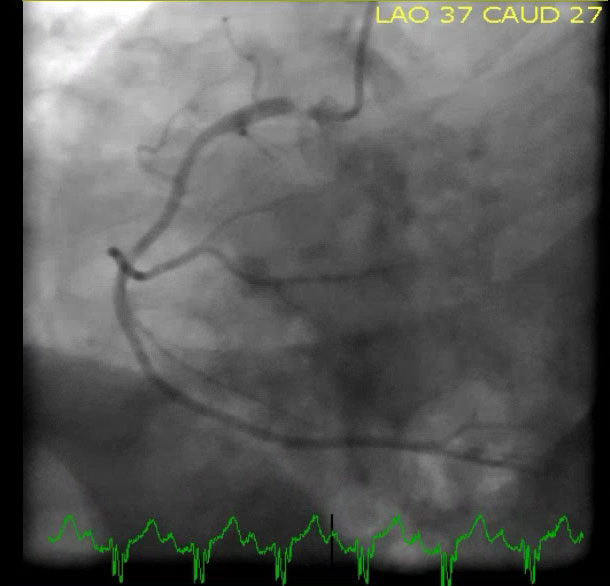

«Катетеризация выявила 100% окклюзию ПМЖВ, которая была успешно стентирована».

«После ЧКВ TnI достигли максимума в 67,10 нг/мл».